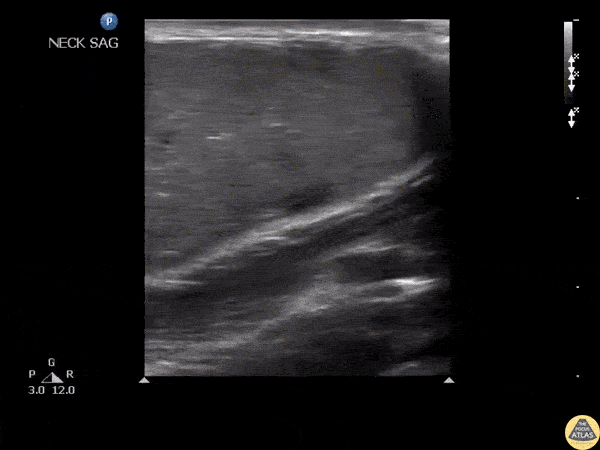

An adult male presented to the ED with a tender mass on his neck with overlying erythema. Ultrasound revealed an epidermoid cyst characterized by the pseudo-testis appearance of the cyst. Image courtesy of Robert Jones DO, FACEP @RJonesSonoEM Director, Emergency Ultrasound; MetroHealth Medical Center; Professor, Case Western Reserve Medical School, Cleveland, OH Original Twitter Post can be found here.